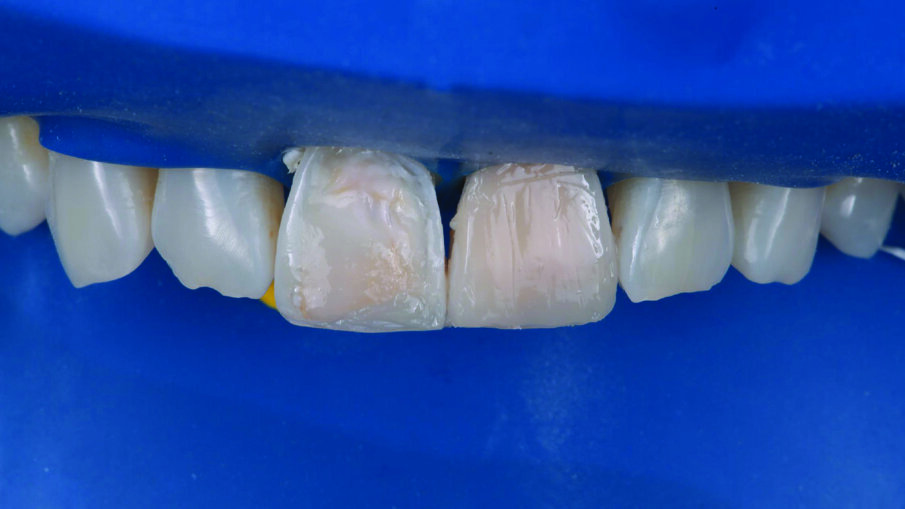

INITIAL SITUATION: Preoperative frontal view of the patient’s teeth, showing severe erosive tooth wear on the vestibular surfaces and incisal edges.

Detailed view of the maxillary incisors. The teeth didn’t show any highly translucent areas, so the use of a single shade/opacity of 3M™ Filtek™ Universal Restorative was selected.

A 1 mm layer of the Pink Opaquer (PO) was placed onto the discolored sclerotic dentin to mask dark areas and light cured for 20 seconds. The material offered a similar creamy handling as the body shades of 3M™ Filtek™ Universal Restorative.

Appearance of the teeth after the first application of 3M™ Filtek™ Universal Restorative A1 shade. No additional body shades were needed (to mask sclerotic dentin) when using the Pink Opaquer.